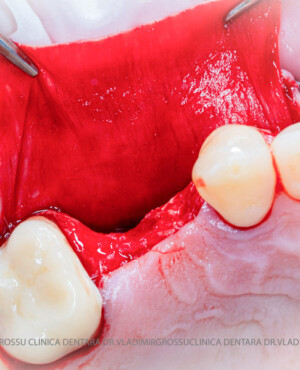

După extracția dentară, în intervalul de 6-12 luni, osul alveolar suferă un proces natural de remodelare, ceea ce conduce la scăderea volumului osos prin rezorbție. De aceea, inserția implantului dentar este ideală imediat după extracție sau, cel târziu, în primele 3-4 luni după aceasta.Scopul procedurilor de adiție osoasă este refacerea fundației osoase necesare pentru stabilizarea corectă a implantului dentar. Pentru ca un implant să reziste în timp la forțele masticatorii, este nevoie de o bază osoasă solidă și sănătoasă.

Procesul de refacere osoasă este complex, însă, simplificat, se bazează pe faptul că osul adăugat se integrează treptat, fiind înlocuit parțial cu os natural, oferind astfel suportul necesar implantului.